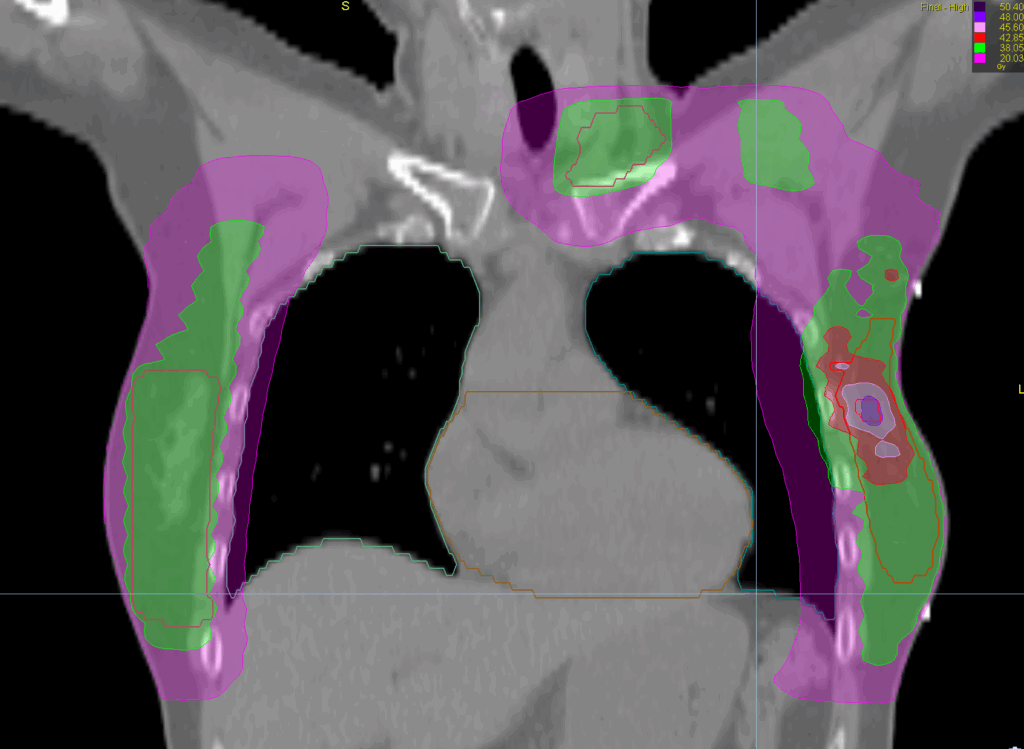

Treatment Plan Images

Fractionation / Protocol Used

40 Gy in 15 fractions

48 Gy (boost)

PTV(s) Volume, Length

1590 cc, 24 cm